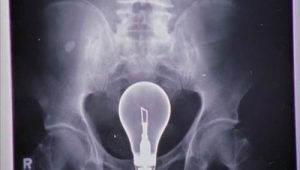

My Urologist

May. 16, 2006